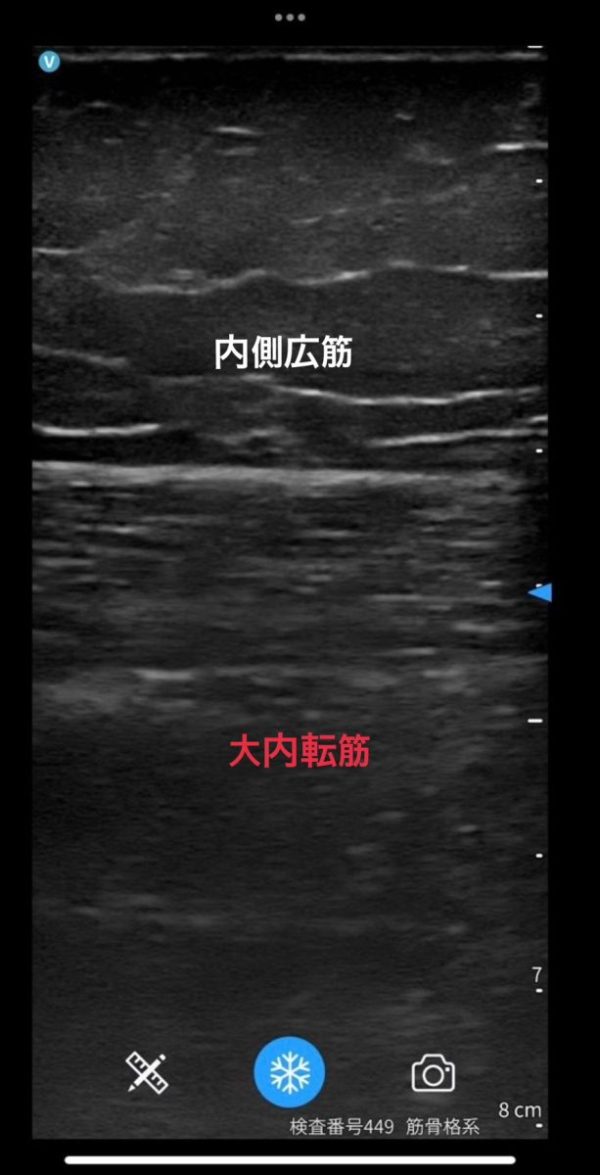

エコーにて筋線維不明瞭の為、

【初診のエコーに比べ、不明瞭ではあるが

筋線維が現れはじめてきている為

シーネ固定と松葉杖でしっかりと筋線維が現れるのを促進します。】